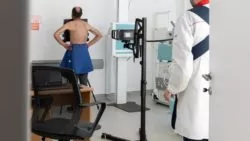

У МОЗ офіційно дозволили виписувати киснезалежних пацієнтів з лікарень

МОЗ офіційно дозволив виписувати киснезалежних пацієнтів. Однак сатурація має бути не нижче 94, а сімейний лікар зобов’язаний надати кисневий концентратор.

Щоб отримати кисневу підтримку в домашні умовах, потрібно, аби лікар зі стаціонару зв’язався з сімейним лікарем пацієнта і переконався, що є вільний кисневий концентратор. Лише тоді хворого на “ковід” мають право виписати додому.